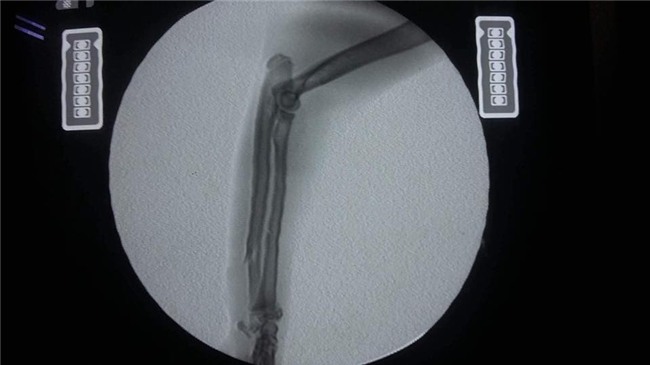

Bé mèo tên là Xù đang được nằm điều trị tại bệnh viện thú y IVET Lạc Long Quân. Bây giờ, bé đang bị liệt nửa người nên chỉ được truyền dịch và thông tiểu. Vì bị thương rất nặng nên bé phải nằm viện 2 đến 3 ngày nữa để hồi phục sức khỏe mới có thể phẫu thuật được.

Đến cả bác sĩ nhìn thấy nó còn thương, không thu tiền phí bởi vì không thể làm gì được cho nó. Đến cả ông Grab nghe tiếng kêu đau đớn của nó còn thương thay mà chảy nước mắt. Lúc chụp X-quang xong dù đau đớn nó vẫn lết về phía mình chỉ để được vuốt ve. Vậy nên cho dù có phải bán hết tất cả những gì mình có thì chấp nhận..